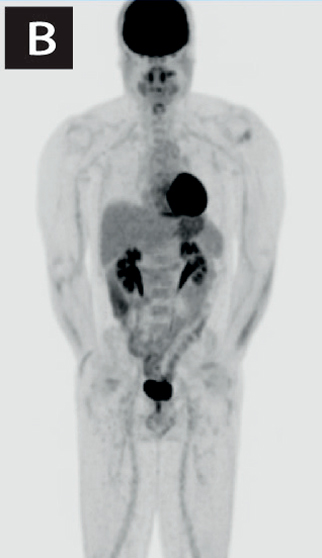

En el seguimiento, se solicitó una tomografía por emisión de positrones (PET-CT) en búsqueda de lesiones en otras regiones corporales. Se evidenció un aumento de captación en sector lateral izquierdo en región selar sin correlato morfológico, lo que es inespecifico. No se evidencian lesiones en pulmones ni en estructuras óseas (Figura 3). Se plantea que el paciente está en remisión, y se continuará su seguimiento.